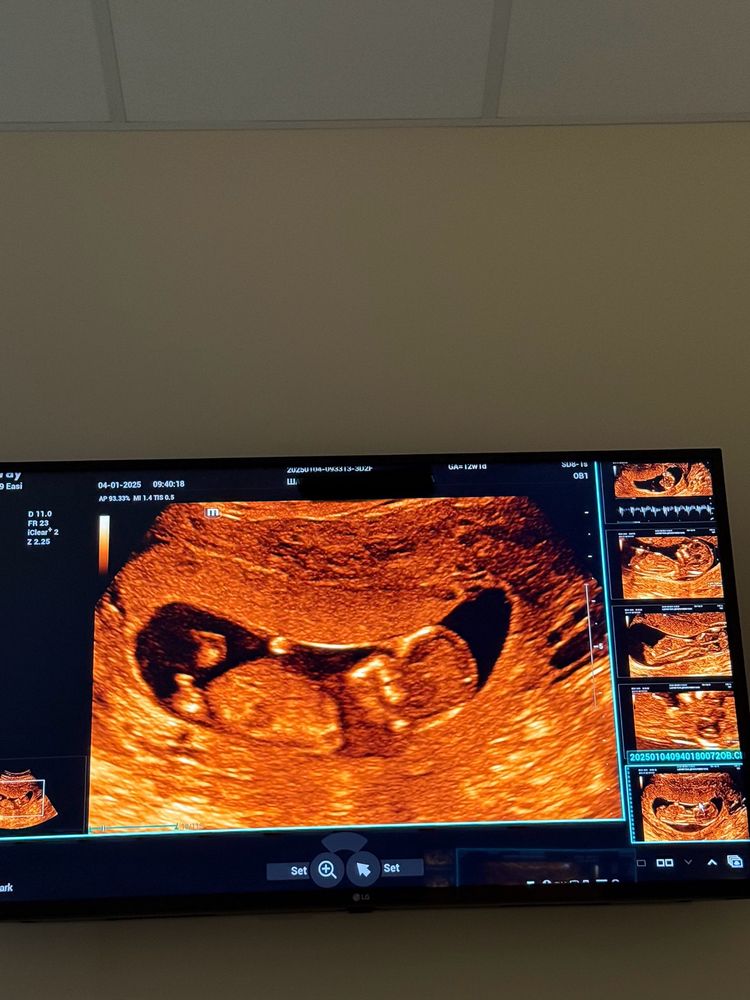

Майя в Благополучная беременность год Не понятно же пол? Пол малыша Девчата, Вообще бугорка нет похоже?🫢 Посмотрите еще 20 записей на эту тему Отменить Ответить За восходом Если по картинку справа внизу смотреть,то мальчик. А на большом не видно. 04.01.2025 Ответить Майя За восходом, 🥲 04.01.2025 Ответить Мария Мне кажется девочка 04.01.2025 Ответить Майя Мария, просто вообще даже намека на бугорок ни на одном фото, не то что угол разглядывать.. 04.01.2025 Ответить Мария Майя, второе фото сверху мне кажется бугорок вниз 04.01.2025 Ответить Майя Мария, 🙏🏻🥲 04.01.2025 Ответить Юлия Ути боже, какая красавица) тьфу- тьфу)) 04.01.2025 Ответить Майя Юлия, думаете девочка?🥹 04.01.2025 Ответить Девочка же? 😀🎉 Девочка💖 Чаты Беременных Выберите чат: Январята-2026 Февралята-2026 Мартята-2026 Апрелята-2026 Майчата-2026 Июнята-2026 Июлята-2026 Августята-2026